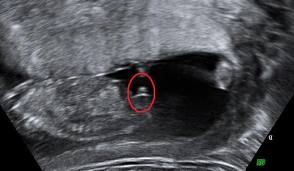

12WEEKS 5 DAYS - Any guesses pink or blue????

I'm not sure if we are seeing the whole nub here. There could be a nub shadow in this one. So for that reason I'm going 50/50, sorry.

The nub isn't fully captured :( Sorry!

Yes it could mean Boy. The nub appears straight in your photos ( looking Girly ) However it looks as though the whole nub is not captured which means there could be more to it.

Here is a perfect example of a "nub shadow",

If you notice the "bubble" portion on the top, sometimes a shadow can be hiding that "bubble" which would allow you to only see the straight nub line underneath. Thus appearing very girly simply because the whole nub wasn't captured.